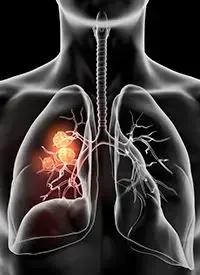

In the study, Warren pooled CT scans from several institutions around the world selected from patients who had undergone image-guided radiotherapy and developed COVID-19 during treatment. In the majority of cases studied, the scans revealed the presence of infiltrates, which refers to the hazy gray areas that can show up on scans of the lungs and serves as a marker of COVID-19 before the patient showed any symptoms.

In the study, researchers reviewed the scans of nine lung cancer patients from Turkey, Spain, Belgium, Egypt and the United States who had tested positive for COVID-19. Warren said, surprisingly, that eight out of the nine patient scans revealed the presence of infiltrates in the lungs.

Identifying COVID-19 is especially important in cancer settings because patients receiving cancer treatment are at higher risk for severe complications and death from COVID. Warren said that although chemotherapy and pneumonia can also cause infiltrates to form in the lungs, the finding in this international study is significant.